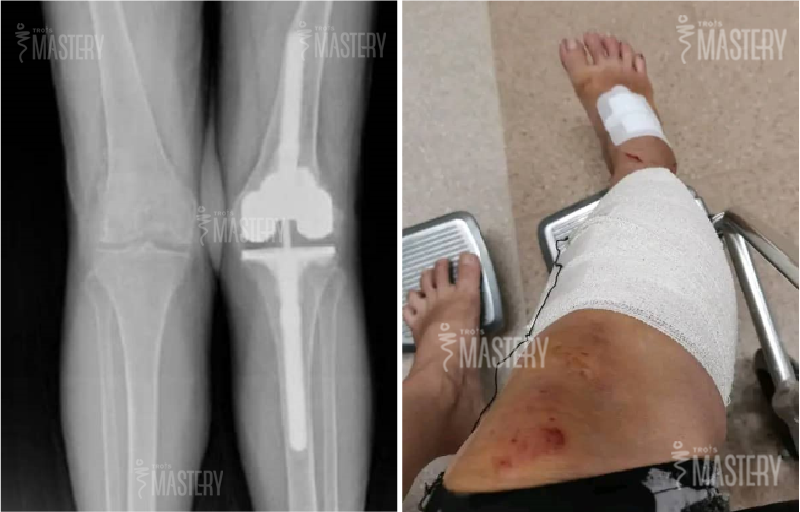

Aimee车祸事故后膝盖的X光片

在2021年MCO期间,Aimee 原是一名餐馆组长,因疫情餐厅停业,被调派为外送员。 某天在送餐途中,不幸发生严重车祸,膝盖板严重裂开,必须紧急手术。

但命运并未就此善待她。连续三次手术皆以失败告终,医生最终告诉她:“你已经属于OKU(残障人士)了。” 并协助她申请了OKU卡。从此,Aimee 的人生仿佛按下了暂停键。